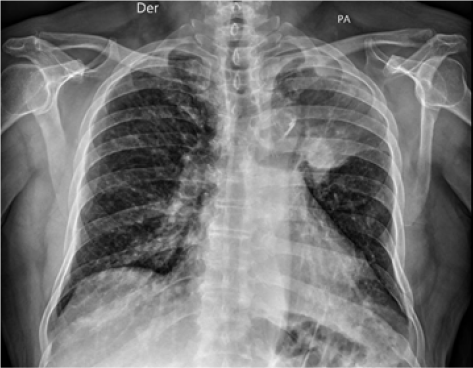

Radiográficamente, se evidenció radioopacidad en lóbulo superior izquierdo que desplaza ipsilateralmente el bronquio principal izquierdo, con criterios de atelectasia lobar superior izquierda (Figura 3). La tomografía resaltó interrupción abrupta del bronquio del lóbulo superior izquierdo asociado a lesión de 3,7 x 3,2 cm que condiciona atelectasia del lóbulo superior izquierdo en relación con proceso neoformativo (Figura 4), nódulos pulmonares de distribución aleatoria, adenopatías cervicales, mediastínicas y retroperitoneales, también lesiones nodulares hepáticas y una lesión que realza con contraste en riñón derecho. Se identificaron adenopatías en los niveles II, III y IV derecho y II, III , IV izquierdo. Adicional lesiones de densidad intermedia en el riñón derecho que realzan en la fase contratada (Figura 5A). Lesiones blásticas con probable relación con depósitos secundarios en T5, T10, T11, L3 Y L5 (Figura 5B). Biopsia de la lesión es positiva para adenocarcinoma pulmonar con patrón histológico tipo acinar. Se identificó deleción del exón 19 de receptor del factor de crecimiento epidérmico (EGFR).

Figura 3.

Radioopacidad heterogénea en ápice pulmón izquierdo.

Fuente: Servicio de Radiología, Complejo Hospitalario Arnulfo Arias Madrid.